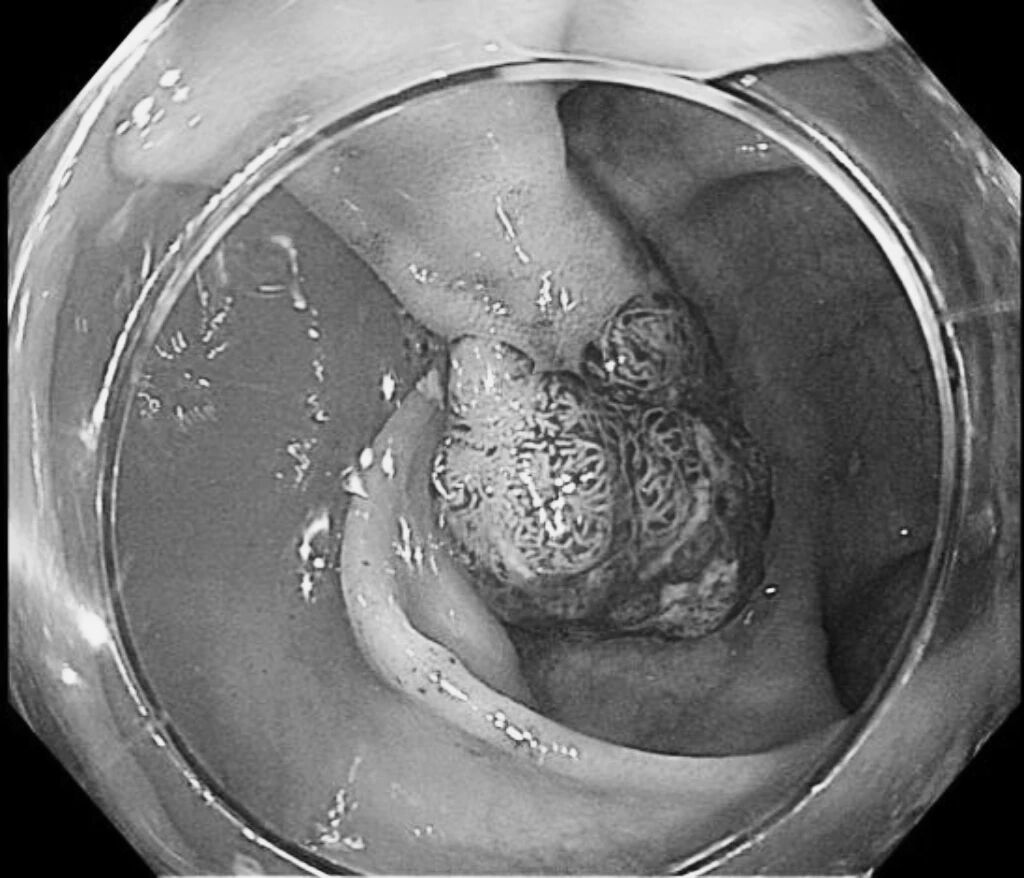

内镜显示患者横结肠息肉情况

手术当天,谭教授凭借精湛的技术,通过内镜精准找到每一处息肉位置。手术过程中,他先对息肉进行染色定位,接着在息肉根部注射靛胭脂溶液,使息肉充分“抬起”,随后用特制的电圈套器稳稳套住息肉,精准切除,最后用止血夹将创面妥善处理好。整个手术过程创伤极小,有效避免了出血、穿孔等风险。